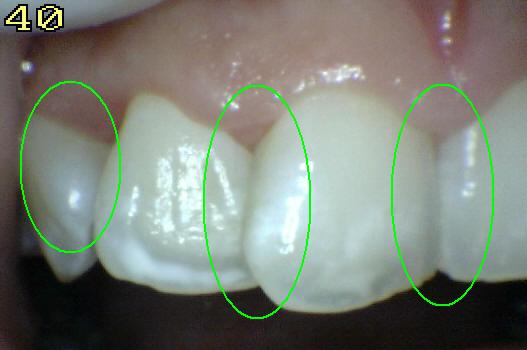

Código 2

(Caries Inicial): Lesión de

caries observada en esmalte en estado húmedo y permanece después de

secar.

- La lesión puede verse directamente desde vestibular,

lingual o palatino.

Mancha blanca / marrón consistente con

desmineralización de esmalte.